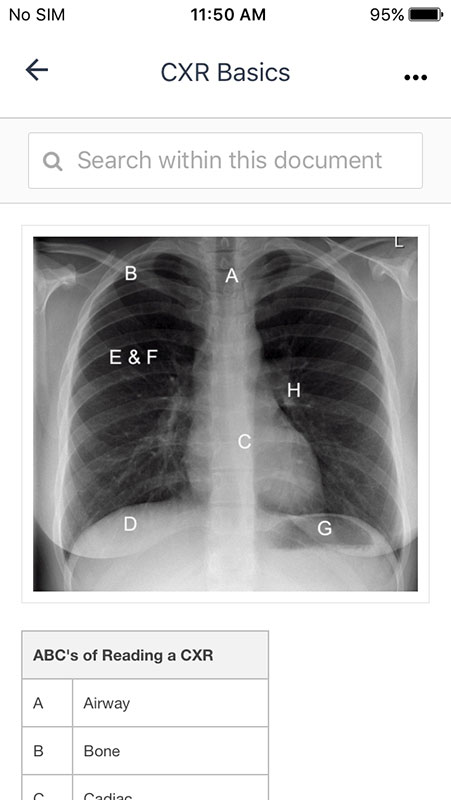

Topics in each section/system basically contain a summary of information about each of the subjects structured in tables/charts rather than comprehensive essays.

This is actually good because the purpose of the app is to be a quick, pocket reference that provides easy-to-follow information in often hectic EM setting.

These tables/charts are the current collection of R.E.B.E.L. EM Reviews, basically medical pearls/board review topics with a purpose to improve medical knowledge and allow physicians to quickly address a particular topic at the point of care.

As you'd probably notice, some of the tables don't look good, meaning they're not optimized for mobile view. Also, images and PDFs cannot be enlarged for a better view.